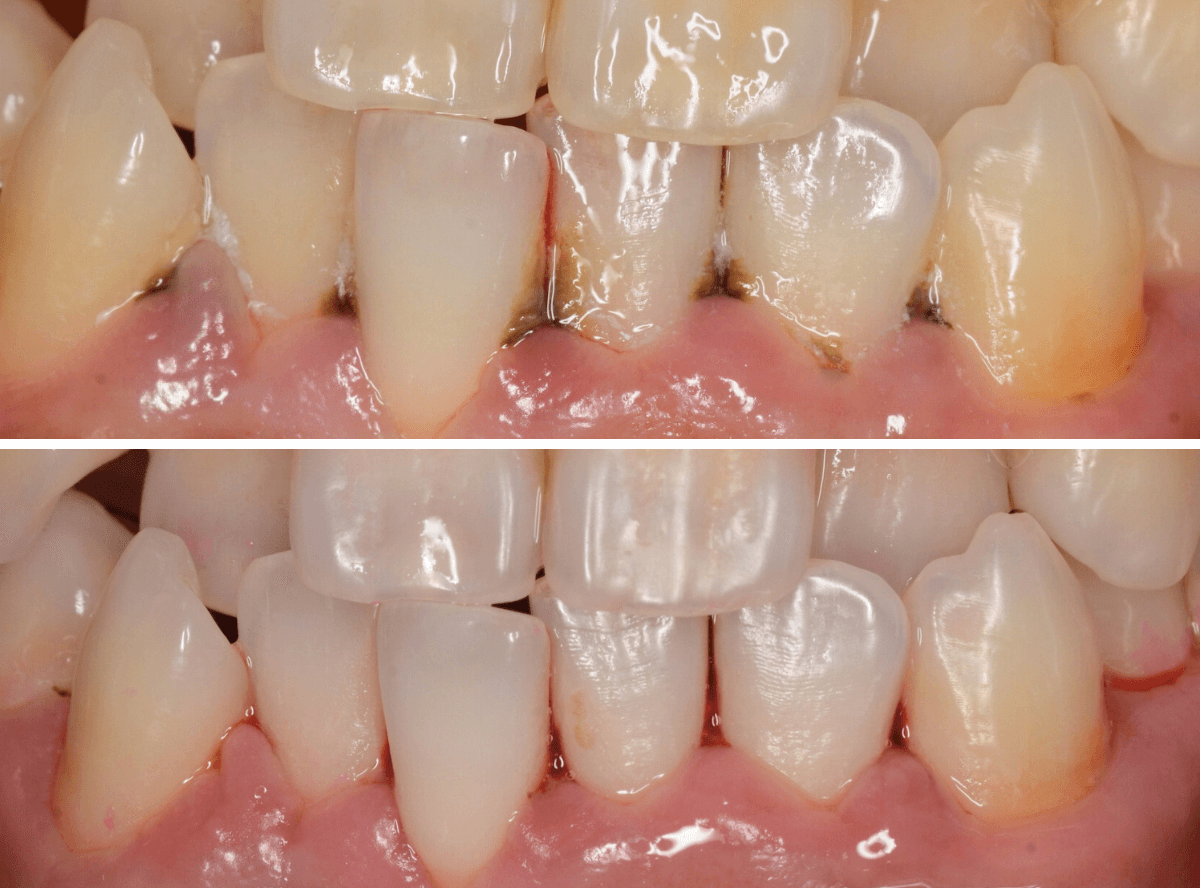

Case.2

今回は、上の前歯の縁下歯石の除去をしたお話です。

写真の左の矢印の歯肉が退縮して腫れています。

右の矢印の歯肉と比べてみるとわかると思います。

こういった歯肉の形をしている部分は、歯石がたまっていることが多いです。

拡大してみると、縁下歯石(歯肉の中に入り込んだ歯石:歯肉に大きく悪影響を与えます)が顔を出しているのがわかります。

かなり歯肉の中に歯石が入り込んでしまっていると思われます。

歯肉の中の歯石は歯にべっとりとこびりつきますので、除去するには麻酔をして引きはがす処置が必要です。

歯石除去後、約1週間です。

歯肉がひきしまってきたのがわかるでしょうか。

治療前との比較です。

比べると、違いがわかると思います。

その後、この患者さんは熱心に通院とお手入れをされて、約二か月が経ちました。

歯肉は順調に引き締まってきました。

歯周治療は、ご本人のメンテナンスなしには結果が出ません、頑張ってらっしゃる形が見えて、とても嬉しいですね

こちらが比較写真です。

並べてみると、治り具合がよりわかりますね